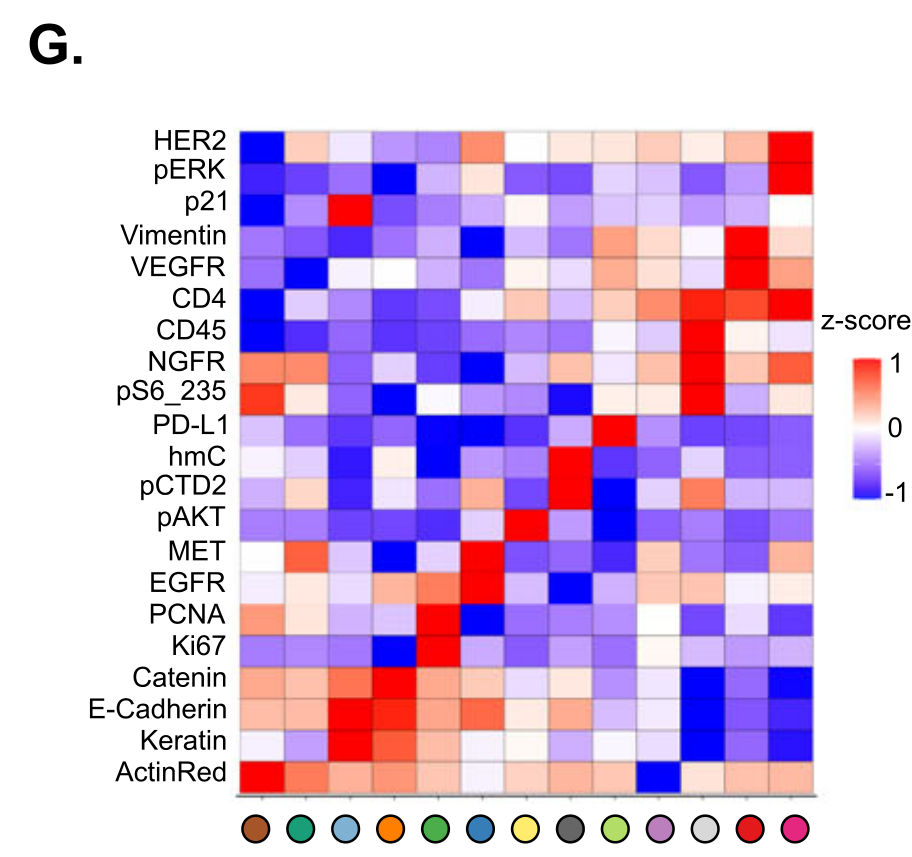

Li X. et al. - 2025

SPEX: A modular end-to-end platform for high-plex tissue spatial omics analysis

Condition Dimension

Categorical

Data Components

Biological AnnotationGene Expression Matrix

Metadata

None

Modality

Proteomics

Resolution of observation

Cellular

Visualized Elements

Statistic

How does expression of a gene differ across patient categories?

Biological

Molecular

Abstraction

Complete

Chart Type

Boxplot

Communicative/Contextualization

Annotation

Comparative Design

Juxtaposition

Layout

Linear

Scalability Strategy

Summay/Aggregate